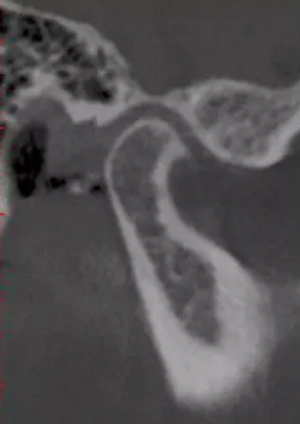

更嚴重的是會影響下頜關節(jié)的健康,正常下頜運動三模式開口運動,側方咬合,前伸下頜,閉鎖合時只留開口運動模式了,其他二種只有先開口后才能發(fā)生。這樣由于上前牙內(nèi)傾,強迫下頜后退,使下頜關節(jié)位置異常,關節(jié)頭越磨越平。這類人群往往有關節(jié)區(qū)疼痛、張閉口彈響,張不開口等,嚴重的會影響日常生活和情緒。

關節(jié)頭損傷